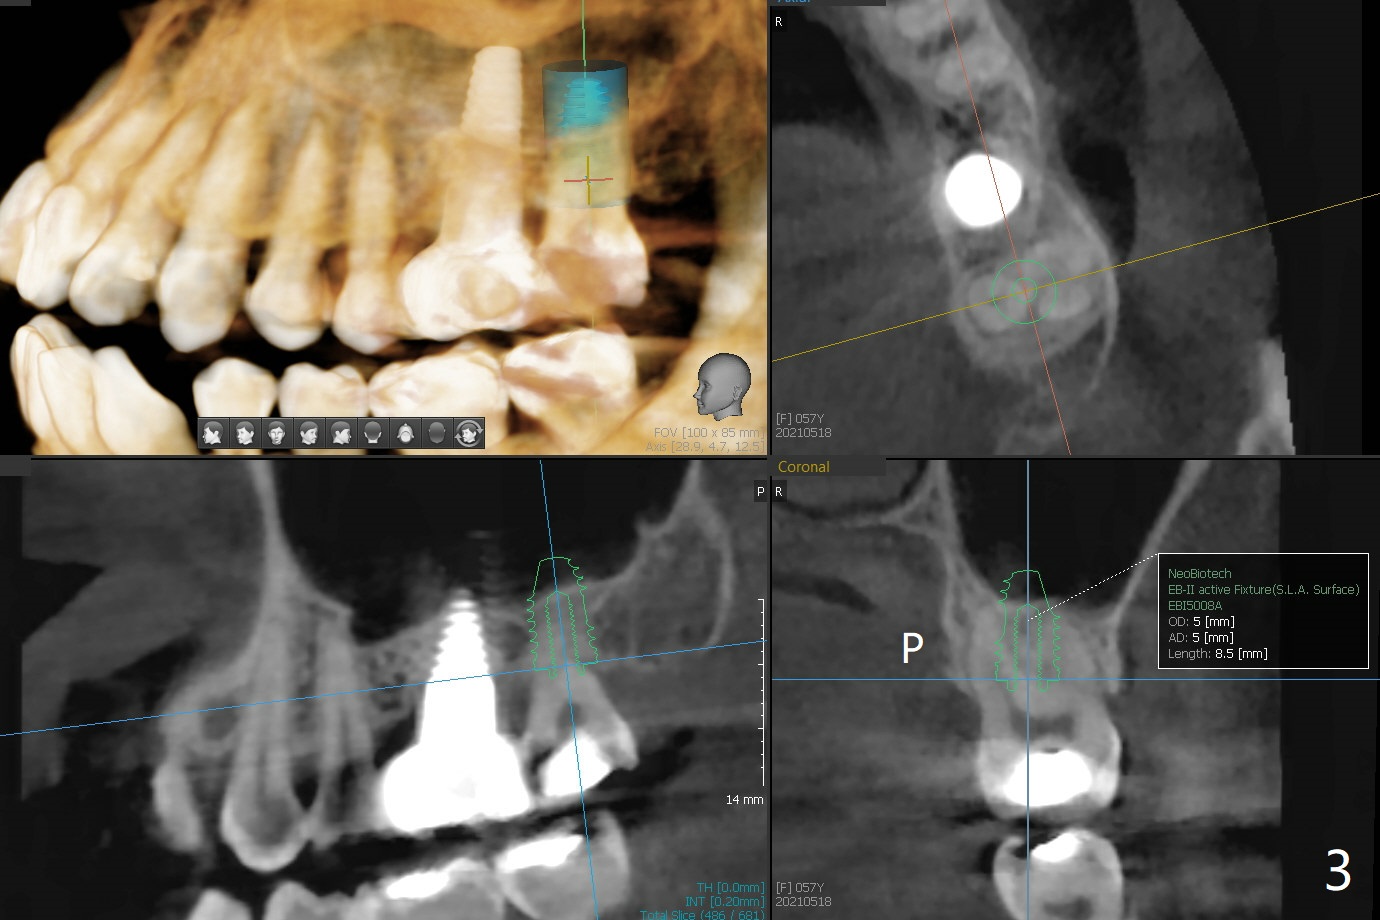

57岁女缺失2号牙多年,八年前14号牙折裂,根管治疗失败,改为即种(徒手),上颌骨骨质高度不足(图一),植体就一定植入上颌窦?近来15号牙又怀疑折裂,不愿接受根管治疗,要求种植。其实14号牙植体植入腭侧牙槽窝,顶端还有骨质,根尖颊侧多个螺纹似乎没有骨质覆盖,但是没有症状。15号牙上端上颌窦膜薄(图三),如果提升时窦膜完整,植入5x8.5毫米植体(图四),否则放置PRF,胶原塞,可以不植骨,植入5x7.3毫米植体(图五)。